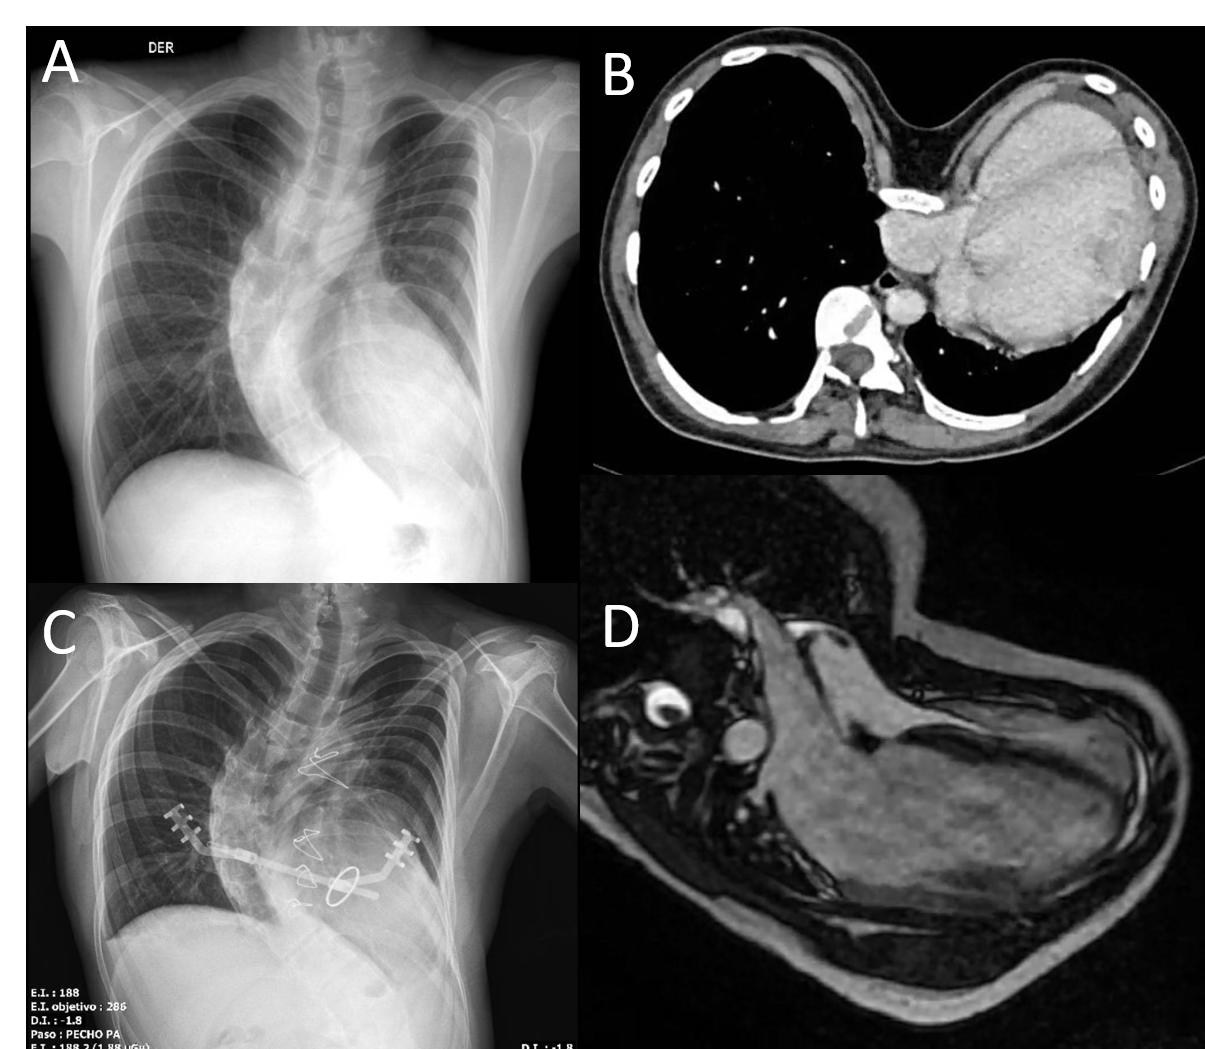

Fig. 2: A-B-C.- Presurgical CMR. D-E-F.- Postsurgical CMR